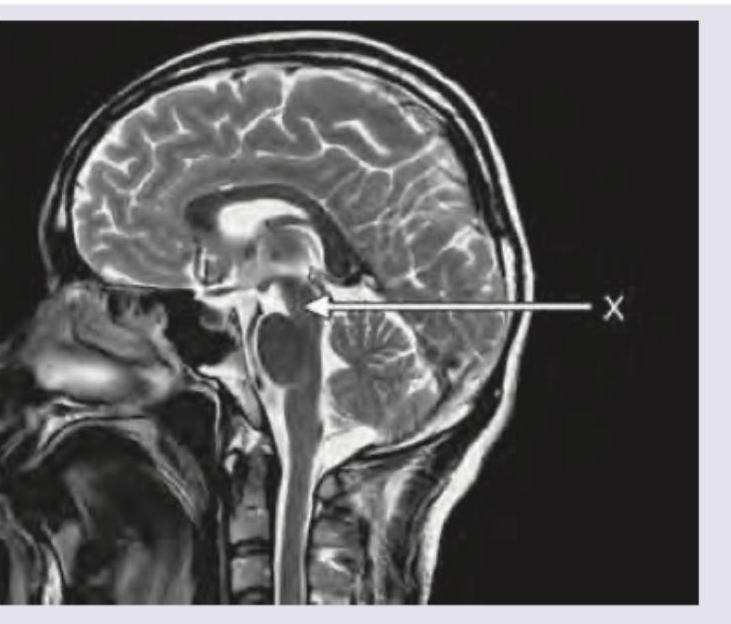

Explanation: ***Pons*** - The arrow (X) points to the **pons**, which is characterized by its **ventral bulge** on the brainstem and its position superior to the medulla oblongata and inferior to the midbrain. - On a sagittal CT scan view, the pons is distinctly visible as a prominent, rounded structure forming the central part of the **brainstem**. *Mammillary body* - The mammillary bodies are small, paired structures located on the **inferior surface of the hypothalamus**, near the midline. - They are much smaller than the structure indicated by the arrow and are situated more anteriorly and inferiorly relative to the midbrain. *Tectum* - The tectum is the **dorsal part of the midbrain**, consisting of the superior and inferior colliculi. - It lies posterior to the cerebral aqueduct, whereas the arrow points to a ventral brainstem structure. *Midbrain* - The midbrain is superior to the pons, and while part of the brainstem, the arrow specifically indicates the **pons**, which is the section immediately inferior to the midbrain and has a more bulbous appearance. - The midbrain would be located just above the structure indicated by the arrow, characterized by structures like the cerebral peduncles ventrally and the tectum dorsally.

Explanation: **Pons** - The image provided is a **sagittal view of an MRI of the brain**, and the arrow labeled 'X' points directly to the pons, a key part of the **brainstem**. - The pons is characterized by its **bulbous shape**, located anterior to the cerebellum and superior to the medulla oblongata, clearly visible in this anatomical plane. *Corpus callosum* - The **corpus callosum** is a large, C-shaped nerve fiber bundle found beneath the cerebral cortex and connects the two cerebral hemispheres. - It is located **superior to the structure indicated** by the arrow in this sagittal view. *Mammillary body* - The **mammillary bodies** are a pair of small, rounded prominences forming part of the posterior hypothalamus. - They are located **anterior and inferior to the region indicated** by the arrow. *Pineal gland* - The **pineal gland** is a small endocrine gland that produces melatonin and is located in the epithalamus, near the center of the brain. - It is situated **posterior and superior to the structure indicated**, typically nestled between the superior colliculi.